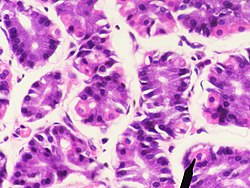

Das Epithel der Magenschleimhaut besteht nur aus einer Zellschicht aus hochprismatischen (höher als breit) Zellen (einschichtiges hochprismatisches Epithel). Die Zellen (Epitheliocyti superficiales gastris) sind durch sogenannte Tight Junctions fest untereinander verbunden. Im Epithel sind zahlreiche schleimproduzierende Nebenzellen eingestreut. Der Schleim dieser Zellen und der der Magendrüsen (s. u.) schützt das Epithel vor der im Magen produzierten Salzsäure.

Die Eigenschicht besteht aus Bindegewebe, Blutgefäßen, Lymphgefäßen, Zellen des Immunsystems (teilweise als Lymphfollikel) und Drüsen. Die Magendrüsen (Glandulae gastricae) münden in die Magengrübchen. Es handelt sich um schlauchförmige (tubuläre) Drüsen. Je nach Magenregion sind diese unterschiedlich ausgebildet und erfüllen auch unterschiedliche Funktionen. Man unterscheidet Kardia-, Fundus- und Pylorusdrüsen. Im Epithel der Magendrüsen sind neben exokrinen Zellen auch endokrin tätige Zellen integriert, die zum diffusen neuroendokrinen System (DNES) gehören.

Fundusdrüsen

Die Fundus- oder auch Eigendrüsen (Glandulae gastricae propriae) bilden den eigentlichen Magensaft. Sie erstrecken sich auf den Magenboden (Fundus) und -körper (Corpus ventriculi). Es sind gestreckte Schlauchdrüsen mit verschiedenen Zelltypen. Diese Schläuche werden in drei Abschnitte unterteilt:

Die Zellen des Isthmus bestehen zum Teil aus Epithelzellen. Sie bilden, wie das übrige Epithel, Schleim (Mucus) und Bicarbonat-Ionen, die als Basen eine Pufferwirkung gegenüber den freien Protonen haben. Dieser alkalische Schleim schützt das Epithel vor dem sauren Milieu des Magens. Weiter in der Tiefe befinden sich Stammzellen, die sich kontinuierlich teilen und die absterbenden Epithelzellen ersetzen.[1]

Im Drüsenhals kommen vor allem Neben- und Belegzellen vor. Im Hauptteil liegen die Hauptzellen und auch einige Belegzellen.

Die Nebenzellen (Mucocyti cervicales) sind iso- bis hochprismatisch und besitzen einen basalen Zellkern. Sie sezernieren ebenfalls alkalischen Schleim zum Schutz des Epithels.

Die Belegzellen (Exocrinocyti parietales, auch Parietalzellen) liegen zwischen den übrigen Zellen oder ihnen außen an. Sie sezernieren Protonen, die sich extrazellulär mit Chloridionen zu Salzsäure zusammenlagern, und den für die Cobalamin-Resorption (Vitamin B12) notwendigen intrinsischen Faktor. Die Zellen bilden intrazelluläre Sekretkanäle mit Mikrovilli. Diese Kanäle werden im aktiven Zustand der Zellen in die luminale (zum Magenraum gerichtete) Plasmamembran eingebaut und vergrößern so die Kontakt- und Abgabefläche. Hier befinden sich Protonen-Kalium-Pumpen, die Protonen im Austausch gegen Kaliumionen aus der Zelle transportieren. Belegzellen sind relativ groß und eosinophil (mit Eosin anfärbbar und daher rötlich).[1]

Die Hauptzellen (Exocrinocyti principales) im Hauptteil der Magendrüsen sind hochprismatisch mit einem basal liegenden Zellkern. Sie bilden Pepsinogene, die Vorstufen verschiedener Enzyme, die zusammengefasst als Pepsine bezeichnet werden (bei Wiederkäuern das Lab). Sie werden in sogenannten Zymogengranula in den Zellen zwischengespeichert. Hauptzellen sind durch den großen Anteil an rauem Endoplasmatischem Retikulum (rER) basophil (mit basophilen Farbstoffen anfärbbar, daher bläulich).[1]